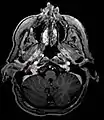

Glomus jugulare tumor

Ectopic functional paraganglioma (glomus jugulare) in a patient with VHL. T2 weighted MRI at the same location demonstrates a high signal mass consistent with a paraganglioma. Extra adrenal paragangliomas can be found in VHL (arrow).